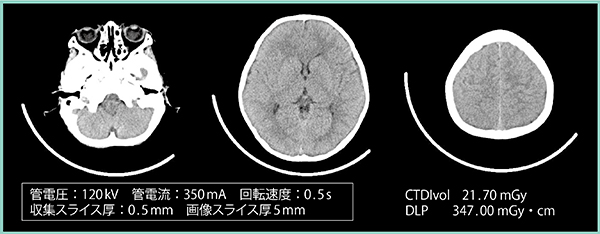

当院では,小児をフットファーストで寝台に固定し,エリアファインダの範囲内に頭部が確実に収まるようポジショニングを行い,ガントリの奥から保護者に頭部をしっかりと固定してもらって撮影を行っている。外傷症例が多く,主に出血や骨折,大きな器質的変化の有無を見るが,これらは高コントラストに描出されるため成人の脳梗塞の診断時のような高SDの画像は不要であり,より分解能を意識したモーションアーチファクトを抑制するプロトコールが求められる。そのため,小焦点の短時間撮影を行うが,成人の頭部を想定した直径17cmの硫酸銅の円形ファントムを撮影し,SDを測定してみた。

撮影条件は,管電圧120kV,管電流は小焦点優先のため350mAの一定とし,収集スライス厚0.5mm,画像スライス厚5mmで,回転速度を0.5秒,0.35秒,0.275秒と変化させて撮影を行った。

0.5秒ではSD4.9とノイズが低減された高画質が得られるが,実際の撮影では体動が多い印象がある。0.275秒では一般撮影と同等の感覚で撮影可能であるが,SD6.5とノイズが多くなる。将来的にFull IRの「FIRST」が頭部に適用されればノイズの問題は解決する可能性があるので,今後に期待したい。

図4は,上記の条件にて0.5秒で撮影した2歳8か月の小児の頭部画像だが,灰白質,白質のコントラストが付き,出血等があっても診断に支障のない画質になっている。